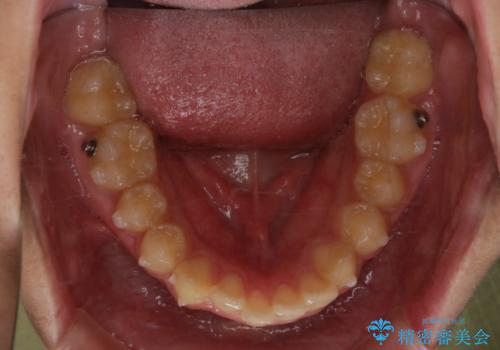

非抜歯で劇的に出っ歯を改善!インビザラインとカリエールの組み合わせ治療

- 矯正装置

- インビザライン カリエール

- 患者様、出っ歯のお悩みで来院されました。

骨格の分析を行ったところ上顎も出てはいるのですが、下顎が引っ込んでいる状態であるということがわかりました。

よって上顎の歯を抜いて治療をするのではなく、カリエールという器具を使用して下顎を前に引っ張り出しながら上顎を引っ込めるという治療を行うことにしました。